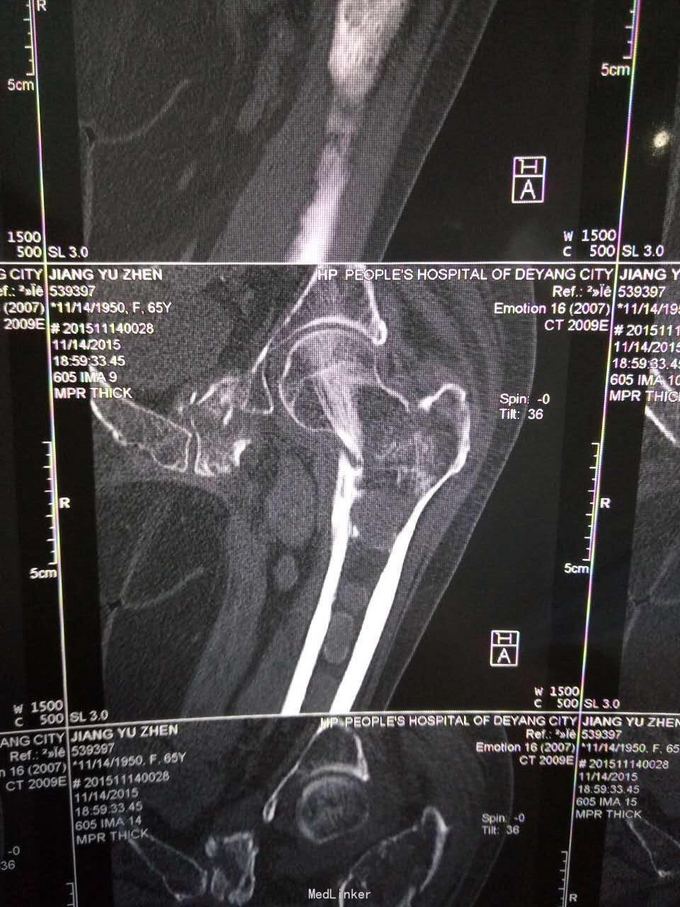

查体,左下肢外旋畸形,髋部压痛,轴向叩击痛。 x片提示:左股骨颈、转子间骨折,左股骨耻骨上支,耻骨联合、下肢粉碎性骨折。

诊断:左股骨颈、转子间粉碎性骨折,左耻骨上支、耻骨联合、下支粉碎性骨折,重度骨质疏松症, 处理:患肢制动,牵引,注射鲑降钙素,科室讨论意见为行髋关节置换术,与换方沟通后,换方表示拒绝手术治疗,主动出院。